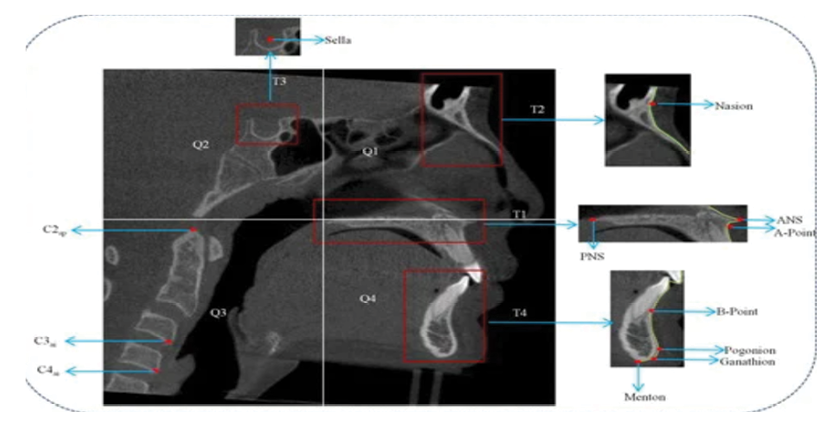

1- Sella (S): The midpoint of the pituitary fossa (Figure-1)

2- Nasion (N): The most anteriorly projecting point on the nasofrontal suture in the sagittal plane (Figure-1)

3- Pogonion (Pog): The most prominent anterior aspect of the mandibular symphysis (Figure-1)

4- Menton (M): The inferiormost point of the mandibular symphysis (Figure-1)

Figure 1. Reference anthropological hard tissue landmarks.